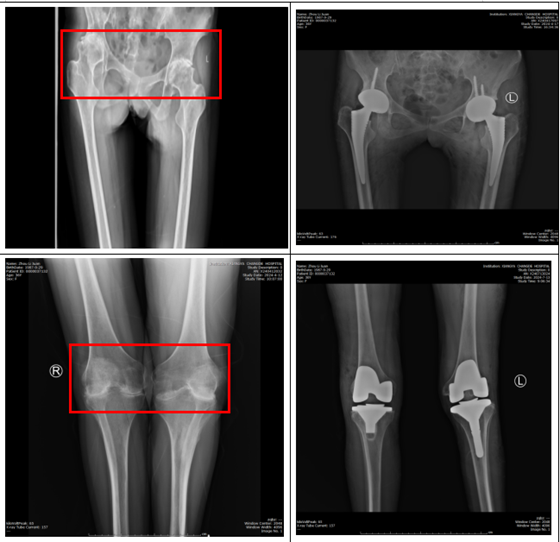

在骨科就诊住院后,关节组主任医师周天宝带领其团队详尽了解李女士的病史和过去治疗情况,结合相关检查确诊为:双侧股骨头缺血性坏死、双膝类风湿性关节炎。由于李女士双侧类风湿性关节炎导致髋关节存在髋臼内陷,膝关节为外翻膝,手术同时涉及到几个大关节,再加上长期服用止痛、激素类药物等,手术难度大、风险高。经过全科讨论决定分批次手术,在周天宝主任医师的带领下,制定了详细、周密的手术计划和预案,于2024年4月完成双侧人工全髋关节置换术,患者及家属对手术疗效非常满意。2024年7月,患者再次来院拟行膝关节手术,为确保手术完美,特邀请中南大学湘雅医院关节外科钟达教授主刀,在钟达教授带领下,团队为李女士完成了双侧膝关节置换手术。术后第二天,李女士便能在医护人员的搀扶下下床自行行走。这一刻,她感受到了前所未有的喜悦与希望。